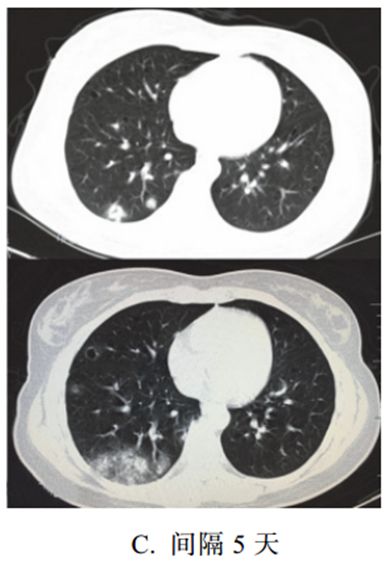

(二)支气管肺炎

支气管肺炎又称为小叶性肺炎,常见于婴幼儿和年老体弱者。

致病菌主要为肺炎链球菌、金黄色葡萄球菌,常可为麻疹、百日咳、流感的并发症。

病变以小叶支气管为中心,在支气管和肺泡内产生炎性渗出。

临床表现为畏寒发热、胸痛、咳嗽、咳痰、呼吸困难等。

影像学表现:

(1)病变多分布于两肺中内带,可见沿支气管血管束分布的斑片、絮片、条索状影(图 3-9),出现树芽征。

(2)病灶可融合成团片状,常伴有局限性肺气肿、肺不张。